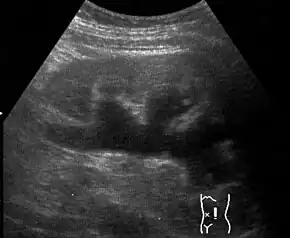

Renal ultrasonography of hydronephrosis[13]